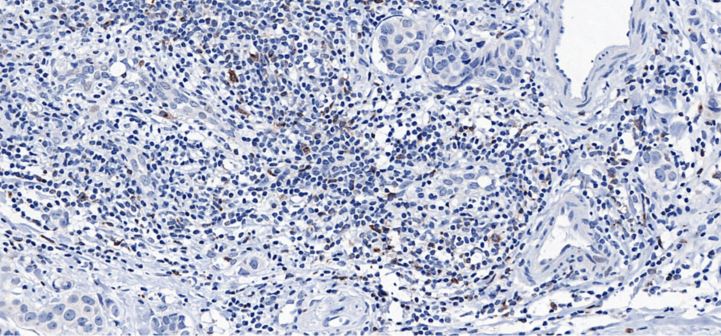

Cytotoxic T lymphocyte-associated antigen-4 (CTLA-4), also known as CD152, is a leukocyte differentiation antigen, a transmembrane receptor on T cells, which shares the ligand for the B7 molecule with CD28, whereas CTLA-4 binds to the B7 molecule and induces T cell unresponsiveness and is involved in the negative regulation of the immune response. Therefore, it plays a role in down-regulating immune response among immune checkpoints and is a target for immunotherapy.

CTLA4 antibody reagents can specifically bind to CTLA4 molecular antigens. Immunohistochemistry kits containing CTLA4 antibody reagents are suitable for predicting the efficacy of immune checkpoint inhibitor therapy (such as ipilimumab) and assessing immune regulatory abnormalities in autoimmune diseases (such as Graves' disease and rheumatoid arthritis).